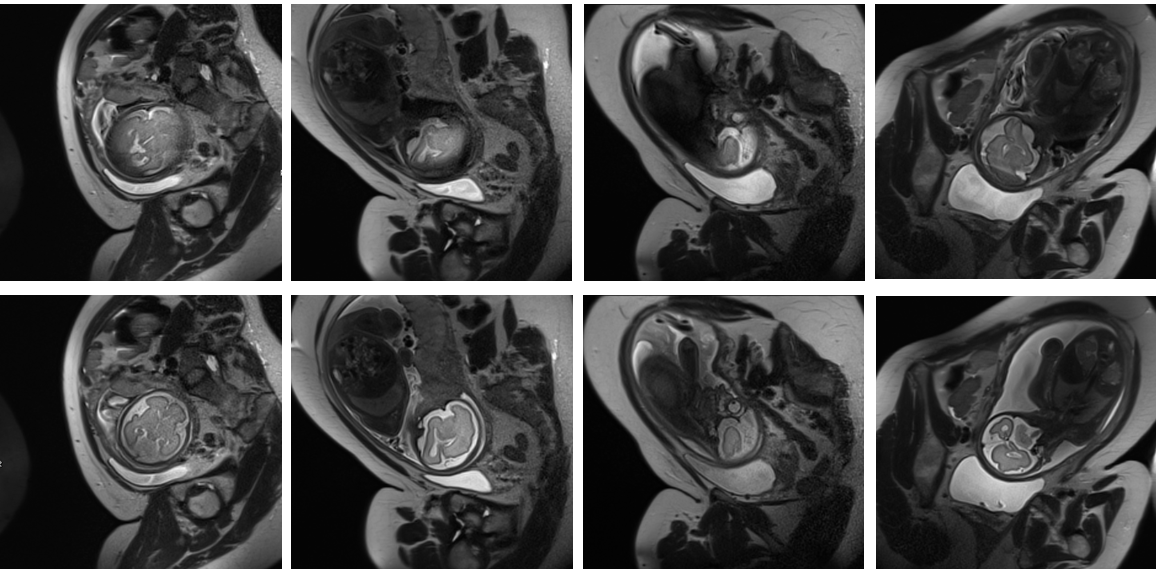

For in vivo study, fetal scans were performed on a 3T MR scanner with Nacq=20,q=0.5formulae-sequencesubscript𝑁𝑎𝑐𝑞20𝑞0.5N_{acq}=20,q=0.5. Fig. 3b shows 4 images from 3 separate scans, where the originally acquired slices (top row) were motion degraded, and the re-acquired ones (bottom row) were not. These results demonstrated the feasibility of online detection of non-diagnostic MR images during fetal scans using the proposed deep learning method.

Refer to caption

(a)

(b)

Figure 3: (a) Number of non-diagnostic slices that are not detected by the IQA pipeline. (b) Four examples from three separate in vivo scans showing motion artifacts in the originally acquired images (top row), and much cleaner images when the same slice locations were re-acquired (bottom row).